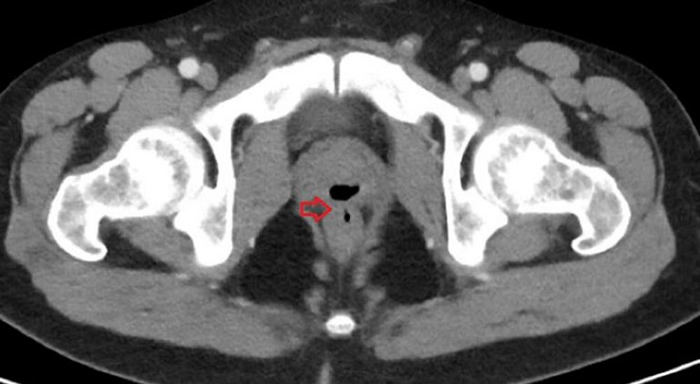

El caso fue tan extraño que aún no lo han identificado medicamente, pero sí apareció publicado en la revista Cureus, donde los médicos cuentan que el paciente tenía un testículo hinchado. Seguidamente, indican que realizaron exámenes posteriores los cuales mostraron signos de una infección del tracto urinario, mientras que un examen rectal digital mostró signos de un problema en la pared rectal. Finalmente, una tomografía computarizada produjo una visión mucho más clara del problema.

Al parecer, este paciente tenía una fístula (un pasaje anormal) entre la uretra y el recto, a través de la cual habían estado pasando varios líquidos y sólidos.